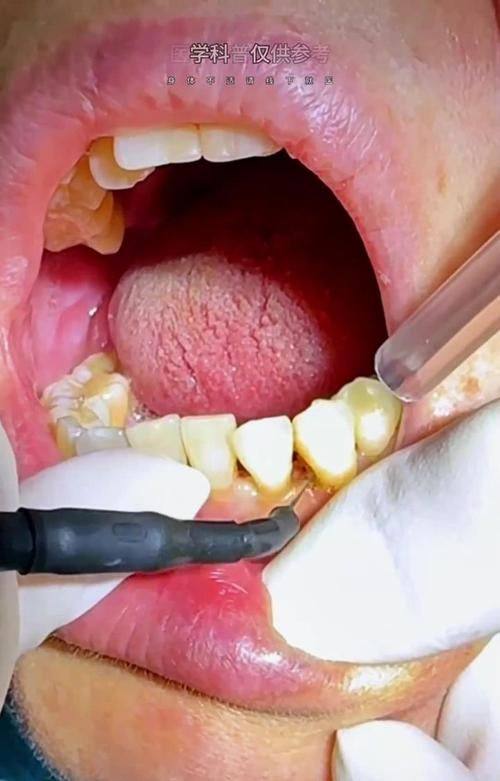

1. 超声波洗牙:利用超声波产生的高频、高能震动,击碎牙齿上的结石和牙渍,实现效率高无死角洁牙,整个过程微痛且轻松。